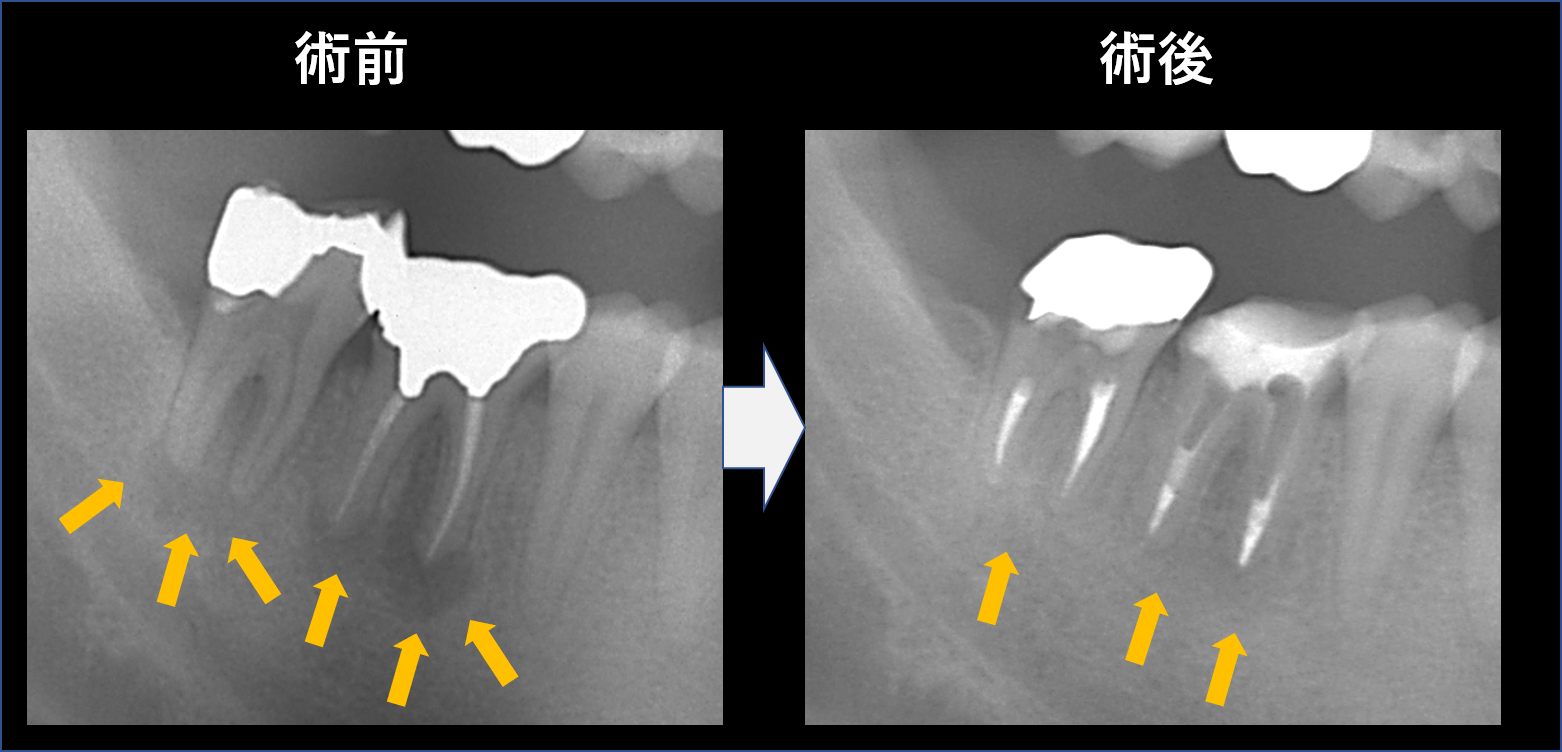

左写真は術前です。オレンジ色の矢印部分に黒い影があります。つまり、根管の中が細菌感染してしまっているのです。

右は根管治療後です。黒い影の部分(感染して骨が溶けている部分)が消失し、骨再生が確認できます。

また、根管治療後は最低でも1ヶ月は経過観察した上で最終的な薬を入れる必要があると考えています。「黒い影(骨吸収)」が大きな場合では、6カ月以上経過観察し、レントゲンで治癒傾向(黒い影が縮小傾向になっているか)を確認してから最終的な薬を入れる場合もあります。

今回のケースも4カ月以上経過観察してから最終的な薬を入れています。